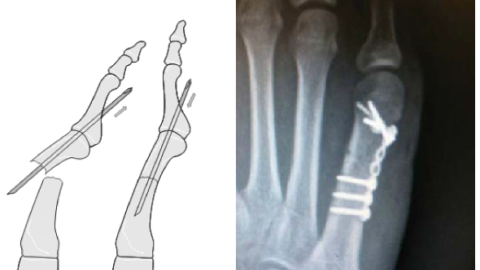

Переломы плюсневых костей

Плюсневые кости представляют собой длинные кости среднего отдела стопы. Их переломы распространены среди людей различных возрастных групп и видов физической активности. Травмы, связанные с этими костями, далеко не редкость в мире спорта. Чаще всего встречаются стресс-переломы или переломы, полученные в результате механического воздействия. Так, стресс-переломам плюсневых костей подвержены в основном бегуны, триатлонисты и ультрамарафонцы. В обычной стопе человека 5 плюсневых костей, которые соответствуют пяти пальцам...